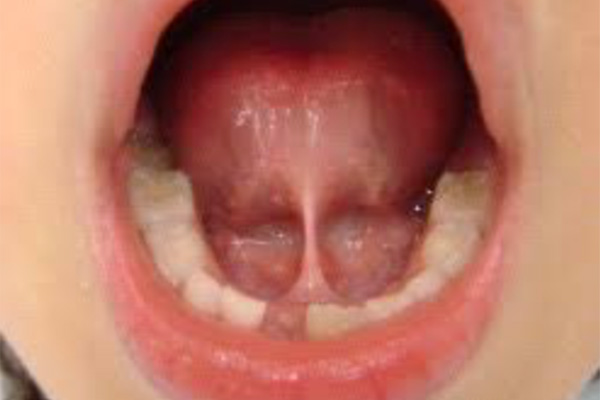

舌小帯/上唇小帯/頬小帯異常

哺乳障害、摂食障害、発音障害、歯列不正、顎の劣成長の原因となる事があります。

年齢、その時の症状の程度によって切除を検討します。